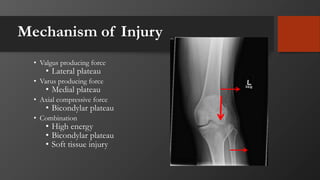

Mechanism of Injury

• Valgus producing force

• Lateral plateau

• Varus producing force

• Medial plateau

• Axial compressive force

• Bicondylar plateau

• Combination

• High energy

• Soft tissue injury